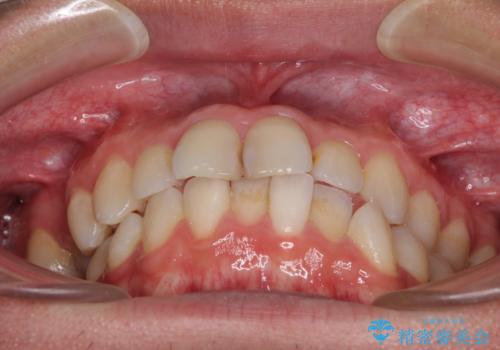

上下の顎骨が左右に大きくずれており、奥歯が交叉咬合となっていたため、ハーフリンガルよりも表側装置をおすすめしましたが、目立たない装置を強く希望されたため、治療期間が長期化することを前提に、ハーフリンガルにて抜歯矯正を行うこととしました。

裏側装置での交叉咬合改善は非常に困難なもので、頻繁に装置の脱落がありました。

それでも想定以上に治療期間は長期化せず、咬み合わせも口元も満足のいく仕上がりとなりました。